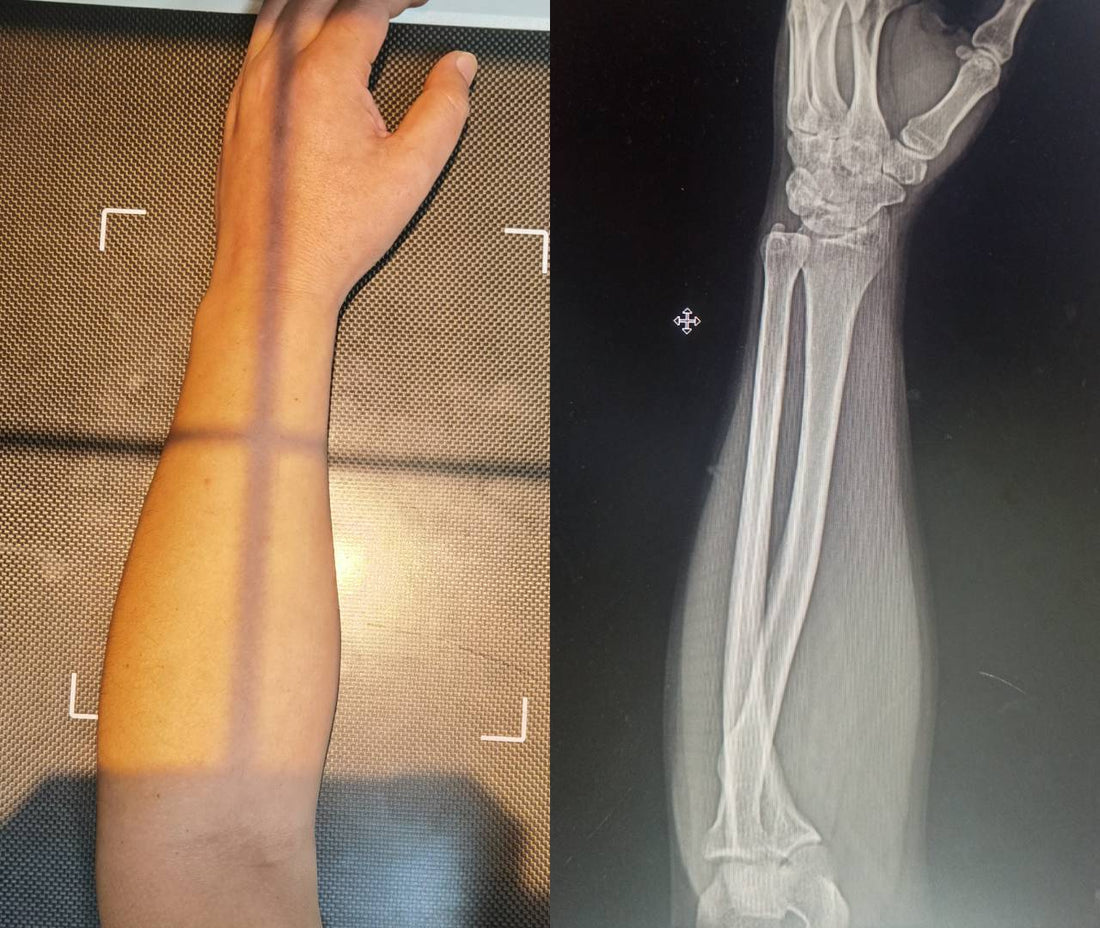

We decided to expose this illusion the simplest way possible: We bought some colored tape, and we fired up an X-ray machine.

(Note: Our brave model for all photos and X-rays is Dr. Sig, who subjected his own arms to radiation for the sake of the truth.)

To show you what is actually happening under your skin, we marked Dr. Sig's forearm bones with tape:

- Orange Tape: The Radius.

- Blue Tape: The Ulna.

We then compared what the Tape (skin) looked like against what the X-ray (bone) looked like in three key positions.

2. The "Real"Vertical Mouse Position

Here is where the marketing falls apart. Most vertical mice (like the Logitech MX Vertical) are not perfectly vertical. They are tilted at approximately 57° to 60°.

If we hold the hand at a true 90° vertical angle, we can't click the buttons effectively. So, we tested the actual position you use with these mice: a 57° inward tilt.

The Reality: Look closely at the X-ray. The bones are DEFINITELY crossed.

Because the mouse is not fully vertical, your arm is still in a state of partial pronation. The Radius (Orange) is still crossing over the Ulna (Blue). It is structurally almost identical to the "bad" flat position, just rotated slightly less.

The marketing diagrams showing straight, parallel lines in this position are erasing anatomical reality to make a sale. At a 57° working angle, parallel bones are physically impossible.